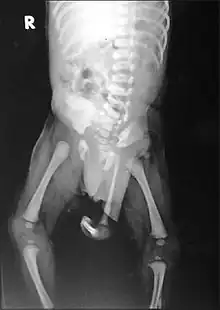

| Radiograph of a human child with polymelia | |

Polymelia is a birth defect in which an affected individual has more than the usual number of limbs. It is a type of dysmelia. In humans and most land-dwelling vertebrates, this means having five or more limbs. The extra limb is most commonly shrunken and/or deformed. The term is from Greek πολυ- "many", μέλεα "limbs".